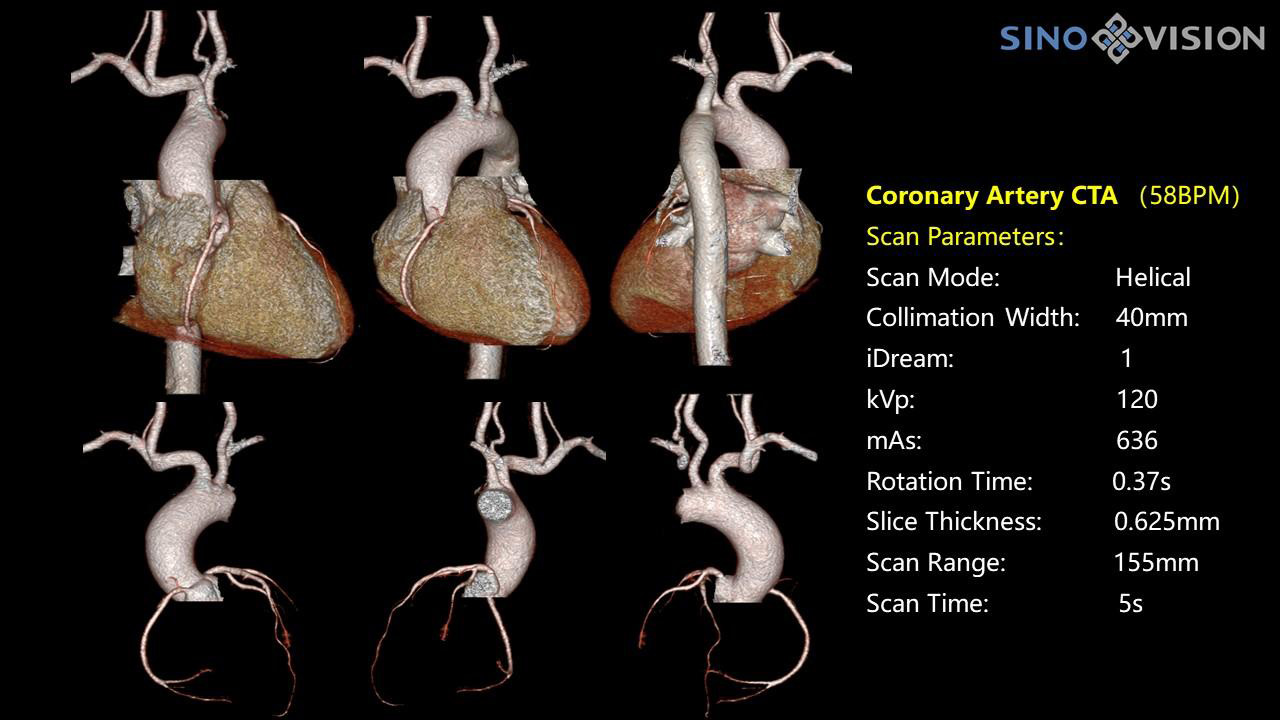

Специализированная технология RTF позволяет уменьшать артефакты движения сердца, обеспечивая максимально точное клиническое изображение.

- Коронарный анализ

- Ретроспективный режим сканирования с ЭКГ-синхронизацией

- Проспективный режим сканирования с ЭКГ-синхронизацией

- Режим последовательного сканирования c ЭКГ-синхронизацией и без ЭКГ-синхронизации